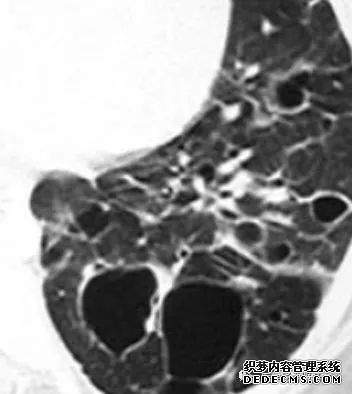

肺转移瘤的十种不典型CT表现